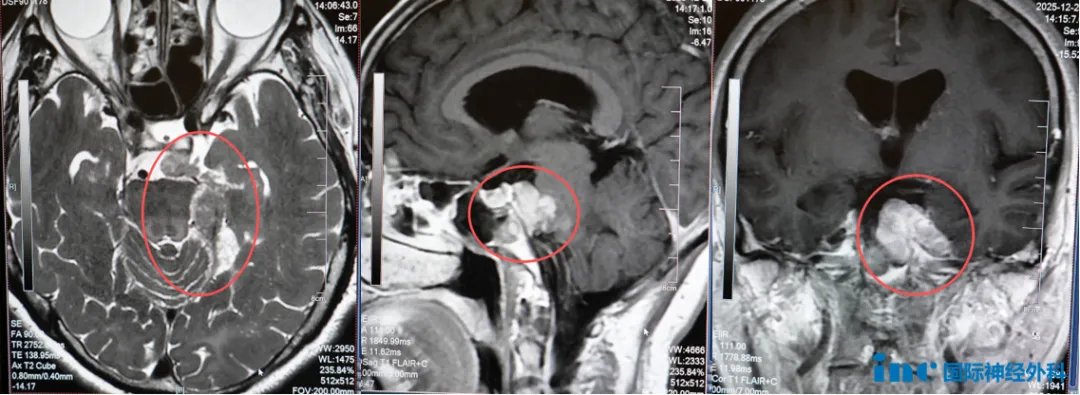

61岁鲁女士左侧桥小脑角区占位,自2003年7月因左侧额部麻木疼痛、额纹消失,发现脑干三叉神经区脑膜瘤,行开颅手术。术后肿瘤残留,相继出现视物颠倒、复视,伽玛刀治疗后发生左侧肢体麻木、乏力。2012年复查提示脑膜瘤复发,行第二次伽玛刀治疗。2018年以来,鲁女士逐渐出现左侧耳鸣、左侧面部持续性麻木疼痛,至2025年症状进一步加剧。巴教授在评估中表示:“在手术中,我们既要争取更大程度切除肿瘤,又要尽力保护神经功能不受进一步损伤。”这番话给予了鲁女士信心,让她最终决定接受这次手术。

22岁小翼神经纤维瘤病Ⅰ型,近年来因脑部肿瘤囊性成分明显增大,症状不断加重:头晕头痛频发,行走不稳,甚至频繁跌倒。面对这样复杂的情况,是否应该立即手术成为了关键问题。在前期远程咨询中,巴教授明确建议进行手术,并表示:“肿瘤囊腔已显著增大,必须尽快切除实体部分并引流囊液,否则脑干压迫将持续加重。”他同时判断,该肿瘤很可能是一种毛细胞星型细胞瘤,若能实现全切除,术后甚至无需进行放化疗。最终,小翼选择手术。